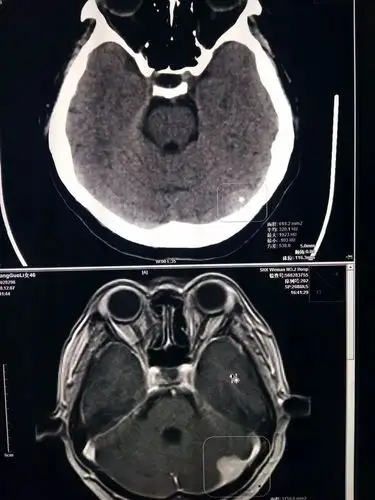

脑磁共振成像(mri),脑瘤

【影像讨论】肿瘤转移还是脑梗死? [病例帖]

进一步完善磁共振检查提示t1 相低信号,左侧脑室前角严重受压.

求医生帮忙,看下磁共振图 脑肿瘤

神经外科赵海康教授会诊后,建议住院做进一步检查,明确诊断.